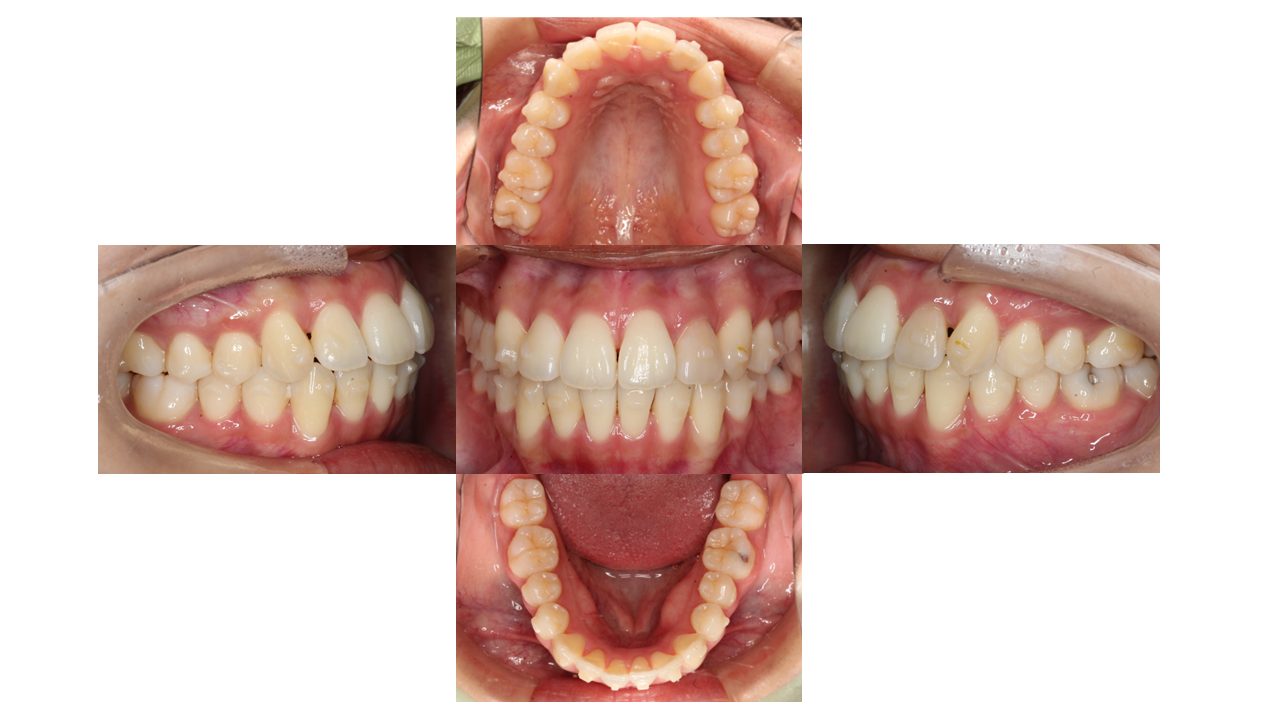

10カ月経過の口腔内の状態です。

歯の表面には、「アタッチメント」と呼ばれる突起がついています。

アタッチメントには、歯とマウスピースのフィットを良くし、歯の動きを助ける役割があります。